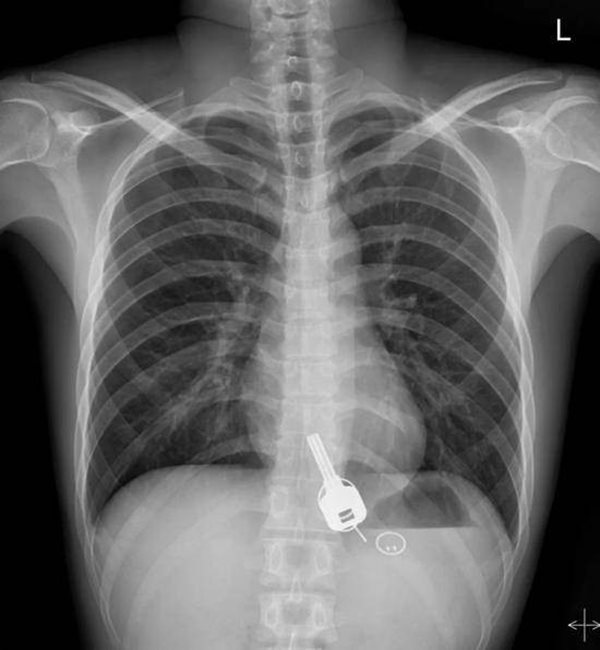

Kết quả kiểm tra cho thấy, nguyên nhân khiến anh Thường bị đau vì phát hiện trong dạ dày có 1 chìa khóa, 2 vòng sắt và 1 thẻ từ. Cuối cùng, thông qua nội soi dạ dày không đau, bác sĩ đã giúp anh Thường lấy những vật đó ra thành công.

Về việc làm sao lấy được vật dụng bằng kim loại kia ra khỏi bụng của anh Thường, bác sĩ Trương Dung Vũ, làm việc ở khoa tiêu hóa bệnh viện Nhân dân Đông Quan cho biết, lúc đầu bác sĩ xem xét và nhận thấy sẽ gặp một ít khó khăn khi lấy chìa khóa ra. Bởi vì chìa khóa không có góc nhọn và sẽ không gây thiệt hại cho đường tiêu hóa quá lớn. Tuy nhiên, nhưng khi nội soi kỹ càng hơn thì phát hiện chìa khóa bị mắc kẹt ở lối vào của thực quản gần cổ họng. Nếu như bị buộc phải lấy ra thì thực quản sẽ bị rách.

Bác sĩ Trương cho biết, nếu như không thể loại bỏ nó dưới ống soi dạ dày thì chỉ còn 2 cách. Một là để bệnh nhân tự lấy bằng đường bài tiết, nhưng do chìa khóa quá lớn và khả năng từ khoang dạ dày đến ruột quá nhỏ sẽ dẫn đến việc gây tắc nghẽn đường ruột. Hai là phải thực hiện phẫu thuật mở. May mắn thay, bác sĩ đã nhanh chóng nghĩ ra một phương pháp khác là đưa ống soi dạ dày không đau vào người. Dưới sự gây mê, các cơ ở lối vào thực quản giãn ra và cuối cùng chìa khóa đã được lấy một cách an toàn.